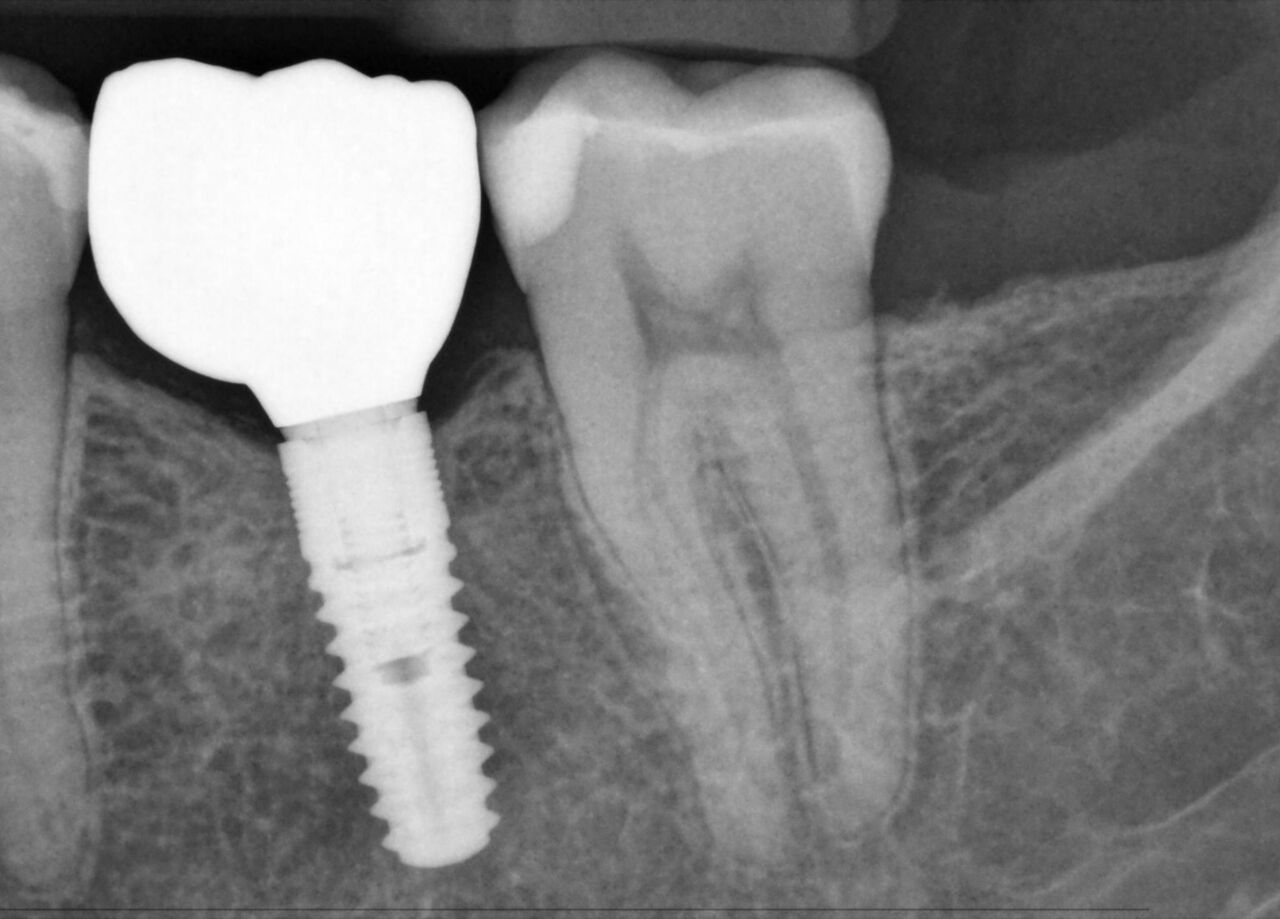

Los sensores intraorales de Dentsply Sirona proporcionan calidad de imagen de vanguardia que apoya el diagnóstico preciso del tratamiento y visión clara de la situación clínica. Respaldado por elecciones expansivas del sistema, mejora de filtro de imagen y servicio de vanguardia y personal de apoyo, los sensores intraorales Xios ofrecen varias posibilidades para su consultorio - brindándole beneficio a usted y sus pacientes.